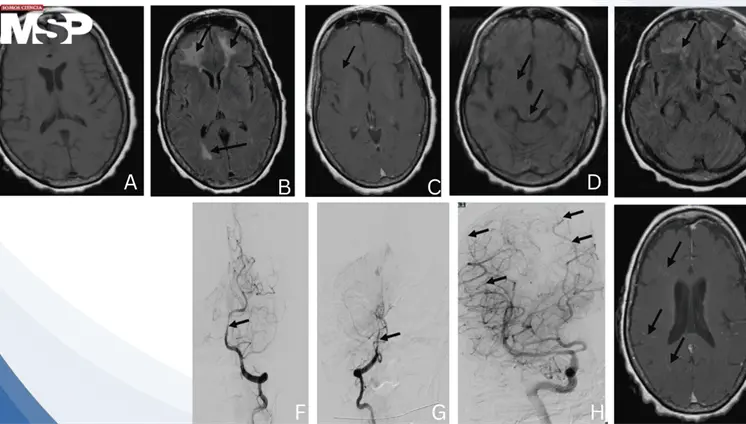

Un dolor de cabeza que empeora al estar de pie y mejora al acostarse es una señal de alerta. Esta cefalea ortostática fue la clave para identificar que no se trataba de migraña, sinusitis ni cambios hormonales, sino de un problema con la presión del líquido que rodea el cerebro.

La enfermedad avanzó de forma silenciosa durante años, manifestándose únicamente con cambios de personalidad, deterioro cognitivo e incontinencia, lo que llevó a un diagnóstico tardío.